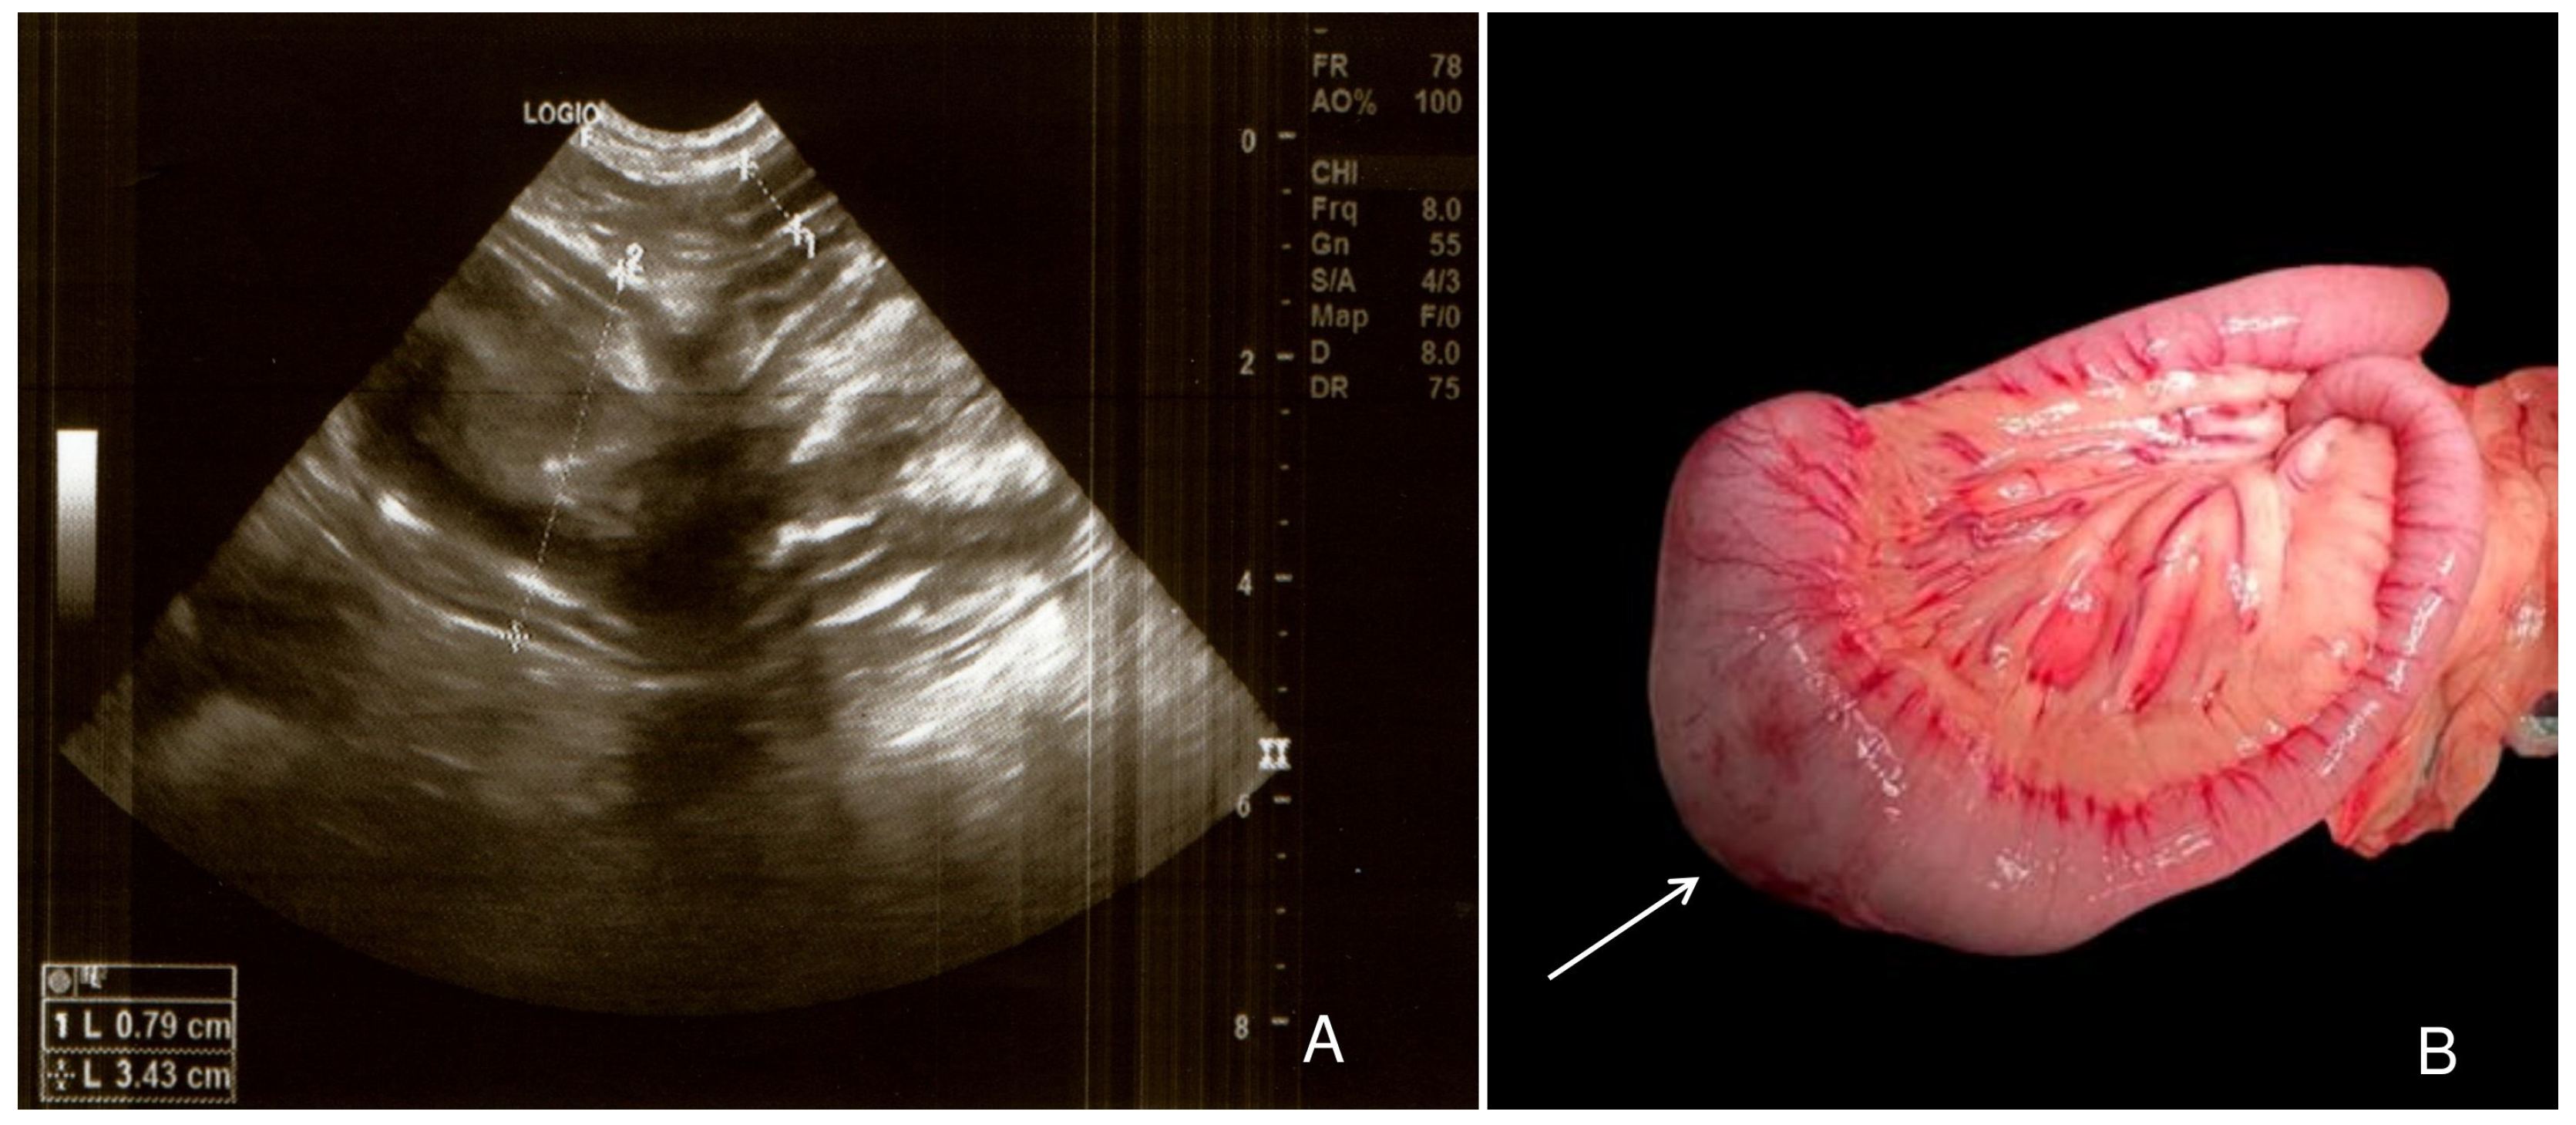

2. Case Description